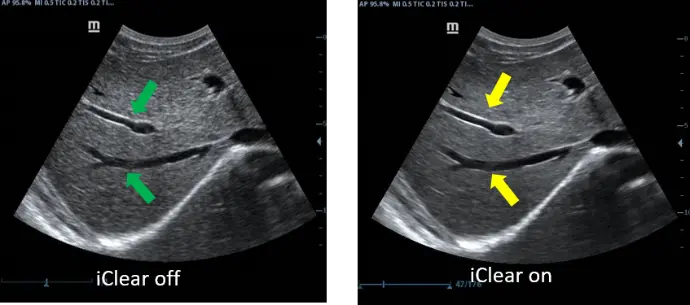

Преносимия ехограф от ново поколение DP-50 Vet е с тънък и ергономичен дизайн, голям FullScreen монитор с качествен “В” и “цветен” образ, както и със стандартно включени множество възможности и софтуери.

Оборудван с PW доплер, Smart 3D и софтуери с автоматични измервания, DP-50 Vet надминава очакванията на всеки потребител. Компакният нов корпус, повишена мобилност и удобство при работа, правят модела подходящ за множество ветеринарни клинични нужди.